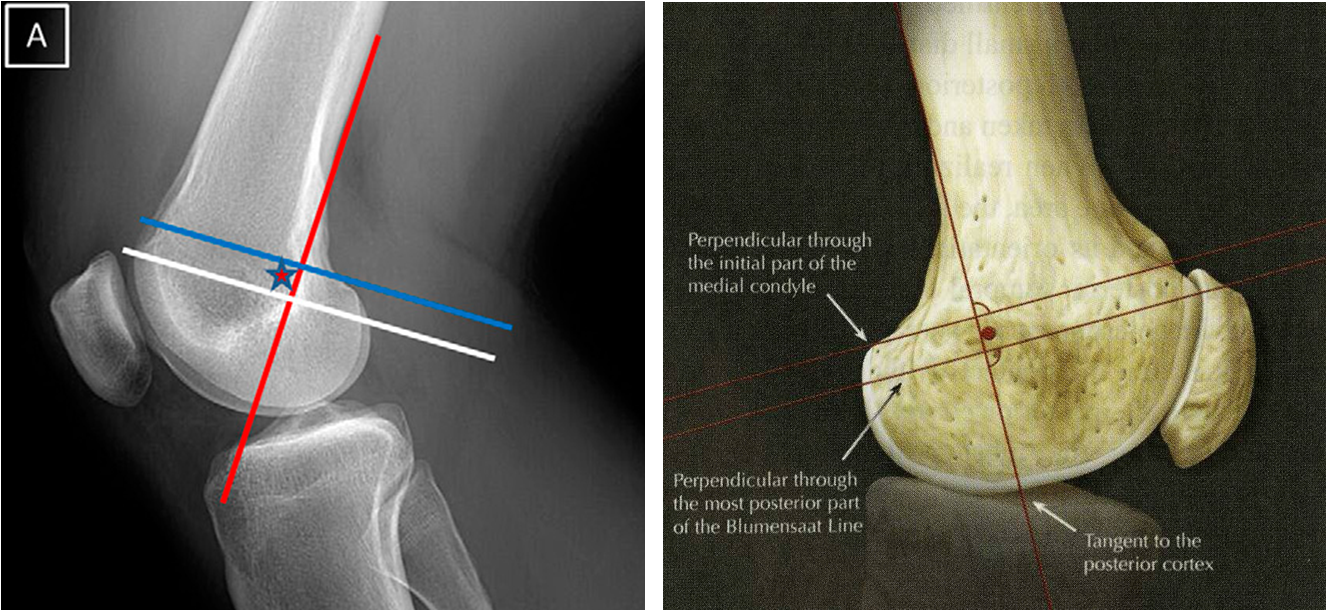

Schottle point라고 불리는 지점은 medial condyle의 끝부분과 blumensaat line의 가장 후방부위를 posterior cortex가 만나는 지점 입니다. 이러한 지점을 Surgeon은 target으로 하게 됩니다. (쉽지 않습니다 ㅎㅎ)